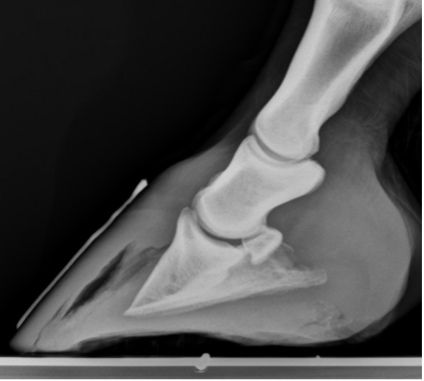

Hoof abscesses can occur after bruising or from penetrating wounds. The abscesses occur when bacteria get trapped beneath the hoof wall or sole, and then multiply. The bacteria create pus, which builds up and creates focal pressure. This can be quite painful, and a horse is often reluctant to bear any weight on the affected foot, especially the heel. Abscesses remain painful until the pus pockets drain and the pressure is relieved. The abscess often follows the path of least resistance to drain, bursting at the heel bulb, along the coronary band, or through the sole.

Check for a smoldering abscess by pressing your finger on each heel bulb and around the coronary band. Feel for heat in the foot and hoof and for tissue softening; also note your horse’s pain response. If you suspect an abscess, have your veterinarian perform an examination including palpation, hoof testers, and possibly nerve blocks to localize the area of concern. They will then open the abscess to establish drainage. It is rare but these sole abscesses can work their way into vital structures in the foot which can impact therapy and prognosis.